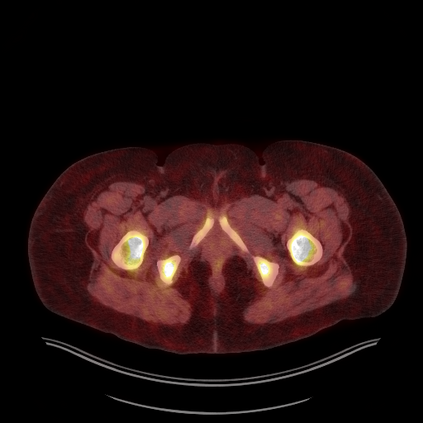

Medical images play a crucial role in assisting diagnosis, remote consultation, and academic research. However, during the transmission and sharing process, they face serious risks of copyright ownership and content tampering. Therefore, protecting medical images is of great importance. As an effective means of image copyright protection, zero-watermarking technology focuses on constructing watermarks without modifying the original carrier by extracting its stable features, which provides an ideal approach for protecting medical images. This paper aims to propose a fragile zero-watermarking model based on dual quaternion matrix decomposition, which utilizes the operational relationship between the standard part and the dual part of dual quaternions to correlate the original carrier image with the watermark image, and generates zero-watermarking information based on the characteristics of dual quaternion matrix decomposition, ultimately achieving copyright protection and content tampering detection for medical images.